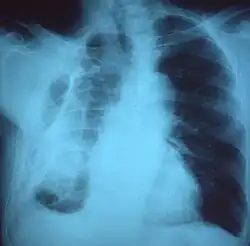

El diagnóstico del fibrotórax suele basarse en una historia clínica adecuada combinada con técnicas de imagen como la radiografía de tórax o la tomografía computarizada.[3] Estas herramientas detectan el engrosamiento pleural y la fibrosis alrededor de los pulmones.[7] La presencia de una corteza engrosada, con o sin calcificación, es una característica común en las imágenes.[3] Las tomografías computarizadas diferencian mejor si el engrosamiento se debe a depósitos de grasa o a fibrosis verdadera.[3]

En casos graves, el pulmón afectado puede perder volumen[7] y el mediastino puede desplazarse hacia el lado afectado.[3] Una reducción del tamaño de un lado del tórax en las imágenes sugiere cicatrización crónica.[6] Los signos de la enfermedad subyacente que causa el fibrotórax también se observan ocasionalmente en la radiografía.[6] Las pruebas de función pulmonar suelen mostrar hallazgos compatibles con una enfermedad pulmonar restrictiva.[6]

Fibrotórax extenso en el lado izquierdo. -

Radiografía de tórax que muestra opacidad heterogénea en la mitad izquierda del tórax por fibrotórax. -